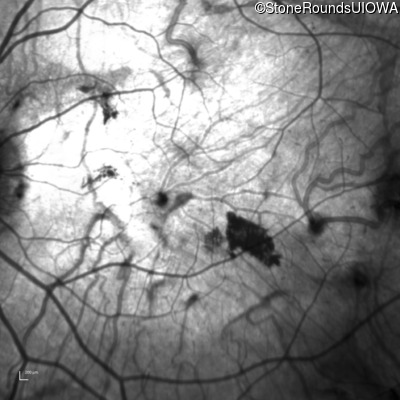

Infrared Fundus Photograph - Left - 20/32 -2

Exemplar